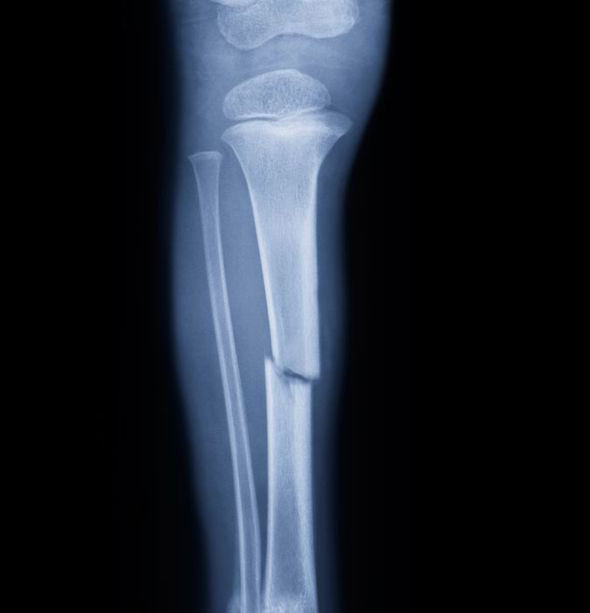

Raziskovalna skupina iz Japonske je v Scientific Reports prikazala rezultate zanimivega poskusa regeneracije poškodovane kosti z matičnimi celicami. Gre za telesne celice, ki imajo sposobnost delitve in diferenciacije v določeno vrsto celic.

Zelo težko je zagotoviti, da bodo v laboratoriju vzgojene matične celice uspešno delovale tudi v telesu. Japonski raziskovalci pa so sedaj prišli do spoznanja, da se v primerjavi z eno samo plastjo celic veliko bolje obnese presaditev dvojne plasti celic.

Znanstveniki so poskus izvedli na miši s poškodovano lobanjo.  Najprej so v laboratoriju na membrano prenesli dve plasti različnih celic. Eno plast so predstavljali mišji osteoblasti. To so odraslemu organizmu lastne celice, katerih funkcija je izgradnja kosti. Drugo plast so tvorile človeške matične celice. Japonci so se odločili za matične celice iz vlaken, s katerimi je zob pritrjen na kost.

Človeške matične celice, ki se bodo preobrazile v osteoblaste, so uporabili zaradi dokazov, da pripomorejo k uspešnosti transplantacije. Membrano z dvojno plastjo izbranih kostnih in matičnih celic so nato presadili na poškodovano lobanjsko kost miši.

Po transplantaciji so opazili, da se kost obnavlja hitreje, kot če bi uporabili samo eno plast celic. Opisana tehnologija presaditve omogoča namreč dvema slojema različnih vrst celic dobro obstojnost na membrani.

Presajene celice so očitno ujete v dvoslojni strukturi in zato dosežejo hitrejšo regeneracijo kosti. To pa je glavni cilj zdravljenja poškodb z matičnimi celicami, ki se obeta nekje v prihodnosti. Več o matičnih celicah vam prišepnemo prihodnjo sredo ob 20.00 v oddaji Frequenza della Scienza.